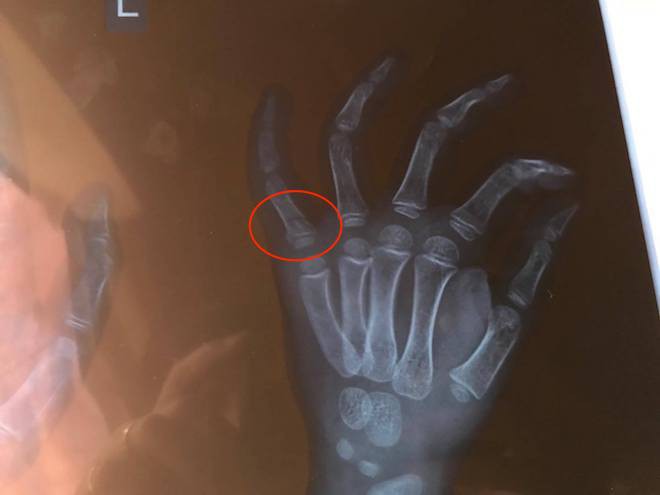

Tuy nhiên, thấy cháu L. khóc vì đau suốt đêm, sáng 26/10, người mẹ đưa con đi bệnh viện khám và chụp phim thì mới hay cháu bị gãy ngón tay út.

Chụp vết xương gãy ở ngón tay út của cháu bé.